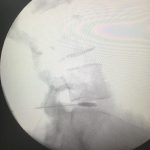

-لیزر(جراحی بسته) دیسک کمری

-اوزون تراپی دیسک بین مهره ای

-درمان تنگی کانال نخاعی غیرقابل جراحی